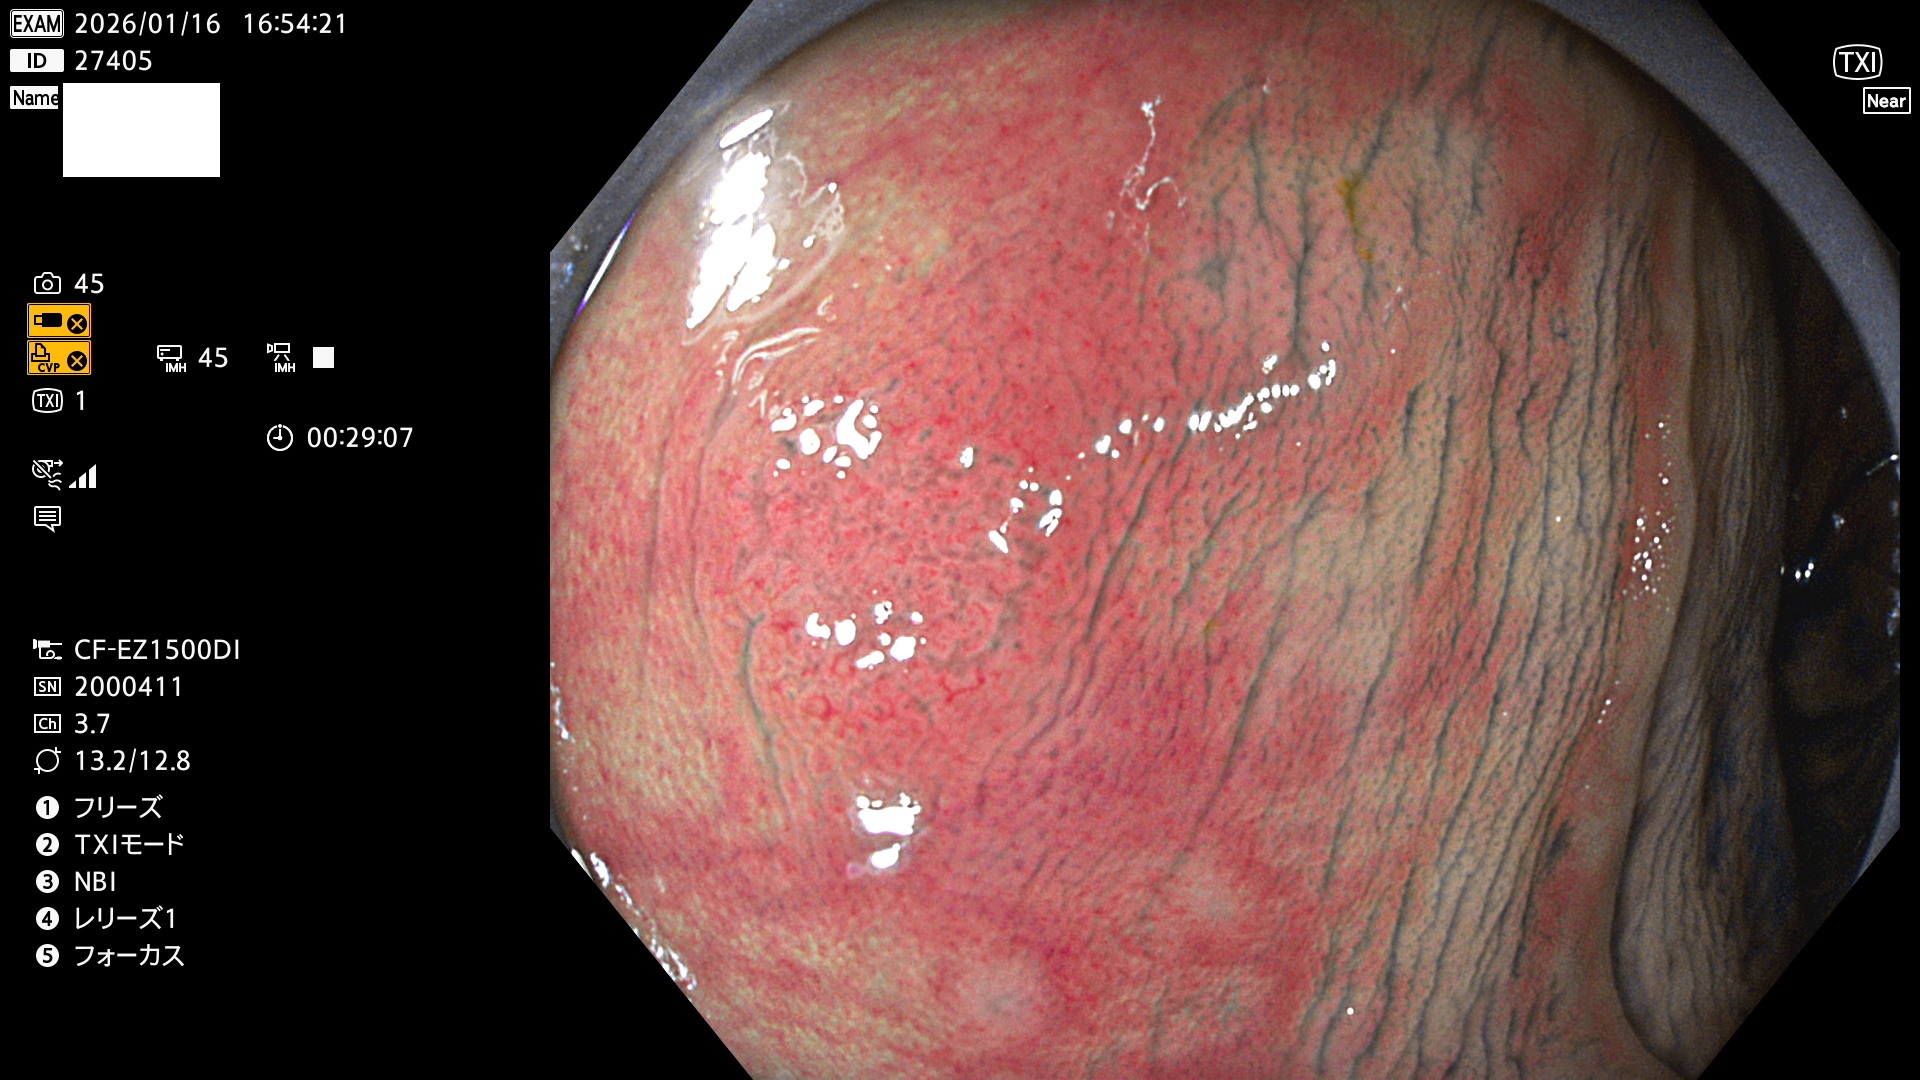

完全に平坦な物をUb、陥凹している物をUcと呼びます。Ubは認識が困難で、Ucはびらん(炎症)と紛らわしいために見落とされやすく、「内視鏡後・大腸癌」の原因になります。

毎週の検査(木・金・土・日)に発見されたUbとUc型・腺腫を、その週の日曜の夜にUPし1週間、提示します。

2026年1月15日〜1月18日の4日間(40件)5個 (Uc_ADR=5個/40人=13%)